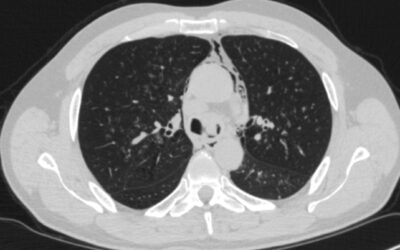

პაციენტი 42 წ მამაკაცი. აქტიური მწეველი. თავს ავად გრძნობს რამოდენიმე თვეა. ჩივილები: ძლიერი ქოშინი ფიზიკურ დატვირთვაზე, ჰაერის უკმარისობა, საერთო სისუსტე. გულმკერდის კტ კვლევით - ორივე ფილტვის ზედა წილებში გაიშვიათებული ფილტვის ქსოვილი, გიგანტური ბულები 10-14 სმ...